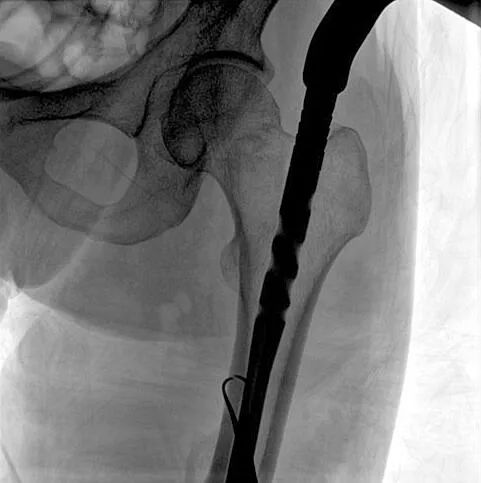

術中使用普愛醫療大平板一體式C形臂進行透視,判斷骨折情況及克氏針、髓內釘等金屬植入物的位置,進行調整。C形臂準確的術中定位,大大縮短了手術的時間,減輕了患者的痛苦,輔助手術順利完成。

在進行髓內釘內固定術時,醫生需要同時觀察到入釘點和骨折部位的情況,普愛醫療大平板一體式C形臂采用30CM×30CM的平板探測器,能夠呈現更廣闊的成像面積,滿足大部分長骨髓內釘內固定術的攝片需求。